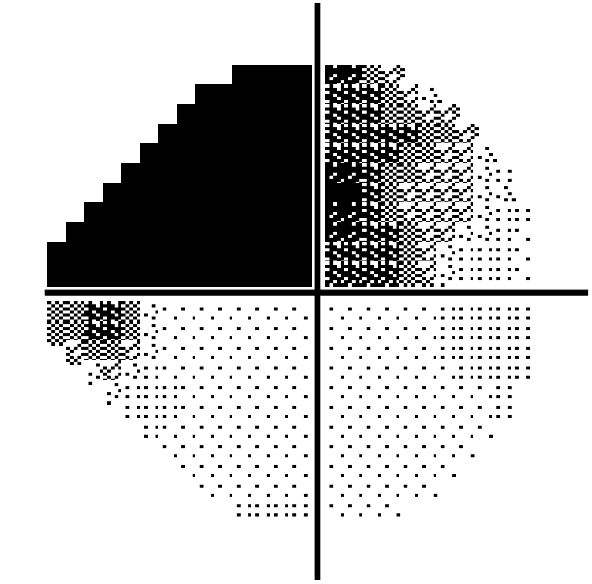

Les logiciels d’analyse permettent d’évaluer précisément l’évolution du champ visuel des patients glaucomateux. Dans le domaine du glaucome, la décision thérapeutique est directement liée à l’appréciation correcte de l’atteinte structurale et fonctionnelle. Déterminer le taux de progression est un pré-requis pour dépister rapidement les patients glaucomateux dont le potentiel évolutif est fort et les traiter en conséquence. La progression du champ visuel, la prise en compte des facteurs de risque, la détection des signes précoces de l’atteinte de la papille et de la couche des fibres visuelles péripapillaires sont alors des éléments déterminants pour la mise en place ou l’adaptation du traitement.